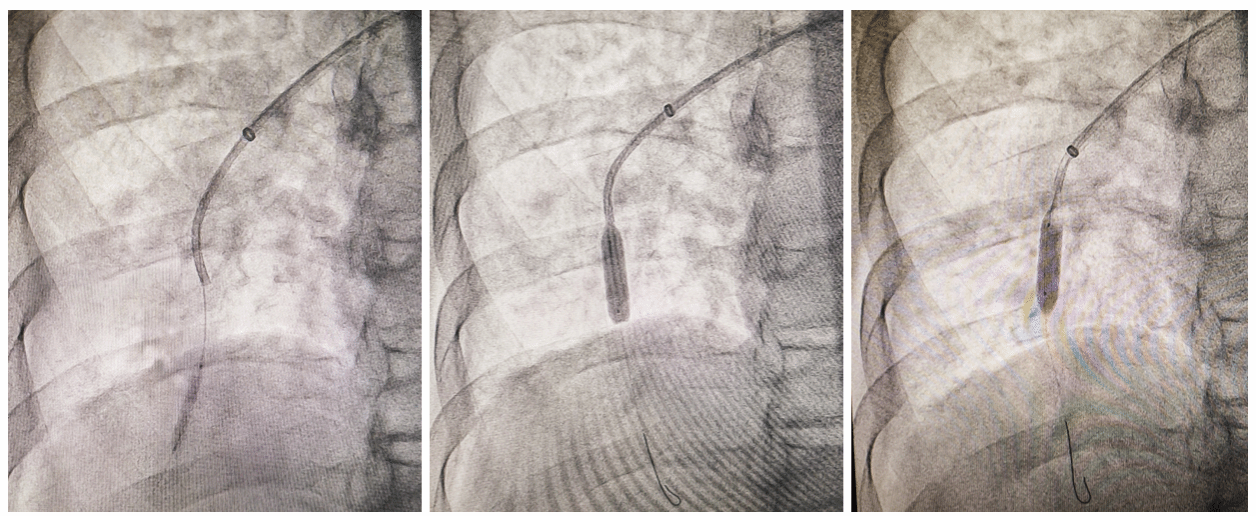

手术当天,介入室内心电监护仪持续运转,张永红主治医师安抚患者:“别担心,我们会精准打通残留堵塞血管。”手术开始后,团队在DSA(数字减影血管造影)引导下,将导管送达残留病变区域,针对不同狭窄部位与程度,先后用不同尺寸球囊逐级轻柔扩张——原本如“枯枝”堵塞的肺动脉,扩张后逐渐通畅,局部造影显示肺动脉显影良好。疏通第2支肺动脉后,患者当即反馈:“胸闷有缓解,感觉舒服多了!”患者术中的积极感受,直观印证了手术的即时效果。

不同尺寸球囊逐级扩张